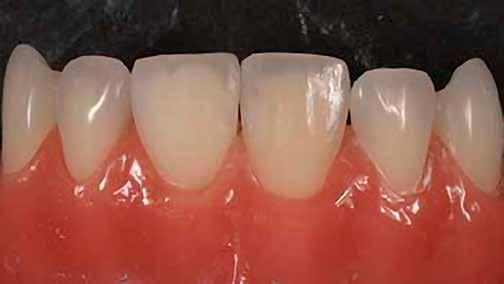

A posterior fogak direkt kompozit restaurációja az egyik leggyakrabban végzett beavatkozás a fogászatban. Az elmúlt években kiemelt figyelem irányult az elérhető eredmények optimalizálására, különös tekintettel a II. osztályú kavitás dobozának (Class II box) kialakítására, és a polimerizációs zsugorodásból eredő feszültség kezelésére. A téma körüli széles körű szakmai diskurzus ellenére van egy olyan lépés, amely gyakran nem kapja meg a kellő figyelmet: a mechanikai formázás protokollja. A mechanikai formázás alatt a restauráció kontúrjának kialakítását, a felesleges kompozit eltávolítását értjük a marginális szélekről, illetve ide tartozik a végső polírozás is. Ez a folyamat három fő lépésre bontható: a felszín oxigén által gátolt, nem polimerizált rétegének eltávolítása, a durva finírozás és a végső polírozás. Jelen publikációban részletesen bemutatjuk ezeket a lépéseket, valamint egy klinikailag hatékony megközelítést vázolunk fel a direkt posterior kompozit restaurációk befejezésére.

A végső polírozás célja egy sima, „zománcszerű” felszín kialakítása, amely a páciens lágyrészei számára komfortos, esztétikailag kedvező, valamint ellenáll a lerakódásoknak és az elszíneződésnek. Ez a folyamat négy fázisból áll.

6. ábra: I. osztályú restaurációk az első moláris és a második premoláris fogakban. A széleken felesleges kompozit figyelhető meg (piros nyilak jelölik).

Finom és szuperfinom, közepes méretű polírozó korongok alkalmazásával 10 000–15 000 fordulat/perc sebességen történik a restauráció peremének polírozása. A korongokat hátrafelé irányuló mozdulatokkal, 45°-os szögben kell vezetni a fog hossztengelyéhez képest.

Finom, gyémánttal impregnált szilikon polírozófejet használunk vízhűtéssel a restaurátum széleinek és a csücsök-lejtők polírozására. Ez a lépés fokozza a restauráció fényét, a karcolások már a durva finírozási szakaszban el lettek távolítva.

Kecskeszőr kefét (pl. Shiny S, https://optident. co.uk/product/shiny-s-goat-hair-brushes/) célszerű alkalmazni stabil nyomással, vízhűtés nélkül, a restaurátum barázdarendszerének polírozására. A polírkefe pumisz pasztával (pl. Vertex® Pumice Plus, https://www.dentaltotal.es/images/ marcas-dentaltotal/VERTEX/CATALOGO_VERTEX.pdf) használandó. Ez a lépés kiküszöböli a barázdákban maradó karcolásokat, amelyek középtávon hajlamosak elszíneződni.

A végső fényesség az 1 mikron szemcseméretű, alumínium-oxid alapú, vízbázisú polírozópasztával (pl. Enamelize®, Cosmedent; https://www.cosmedent.com/product-category/finishing-and-polishing/) érhető el, valamint filc polírozófejek és korongok segítségével. A polírozás fokozatosan

növekvő fordulatszámmal (3000–20 000 fordulat/perc) és csökkenő nyomással történik. A pasztát mindig a fogra/restaurációra kell felvinni, nem pedig a korongra, így elkerülhető a paszta szétszóródása a kezelőben. (Lásd a 10. és 11. ábrát.)

Ezt követően a fogat puszter használatával letisztítjuk, majd a pácienst elbocsátjuk.

Amint látható, ez a protokoll egyszerű és kiszámítható módszert kínál az I. és II. osztályú direkt posterior kompozit restaurátumok tartós, esztétikus felszínének kialakítására (/spear-review/2013/08/evaluating-facial-esthetics-facial-profile).

12. ábra: A premoláris fogak preoperatív állapota.

13. ábra: A premoláris fogak postoperatív fotója.

14. ábra: Egy moláris fog preoperatív állapota.

15. ábra: Egy moláris fog postoperatív fotója.